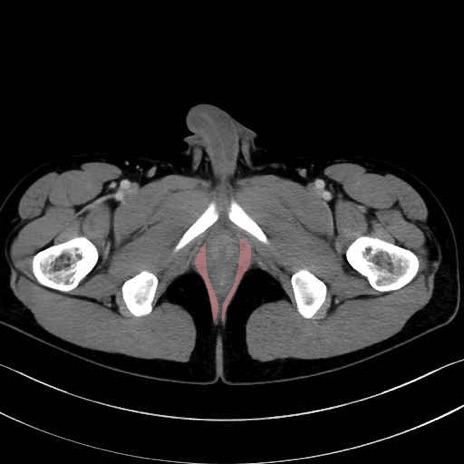

肛門挙筋(levator ani muscle)のCT画像の解剖

肛門挙筋 (Levator ani)